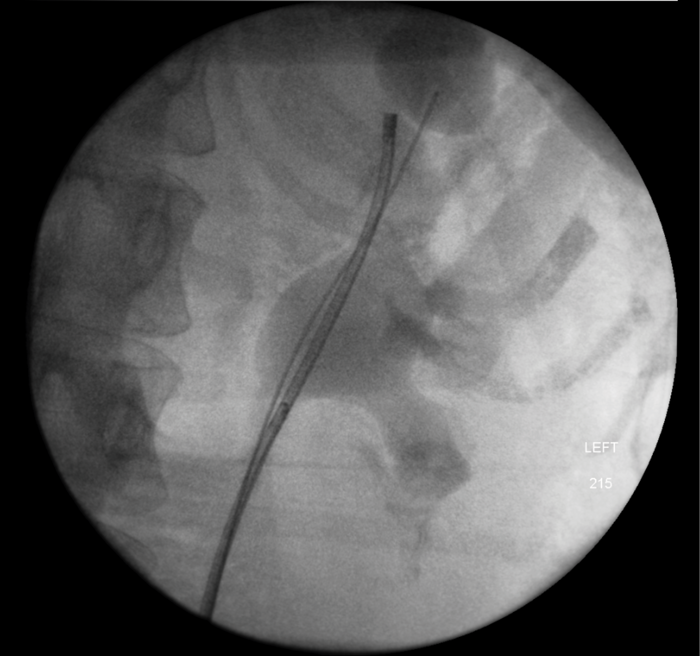

An 80-year-old woman presented with urosepsis requiring direct admission to intensive care. A CT scan demonstrated gas in the collecting system and a nephrostomy was inserted.

Figure 1: CT demonstrating gas in the collecting system.

Figure 2: Nephrostogram showing stone in left kidney with nephrostomy in place prior to flexible ureteroscopy.

The patient made a good recovery from her life-threatening sepsis, retaining function on a DMSA scan and underwent a flexible ureteroscopy to clear the stone. Gas forming organisms in the urinary tract result in dramatic imaging but should not distract from the patient’s clinical condition. A conservative approach may avoid a nightmare nephrectomy in a highly morbid patient.